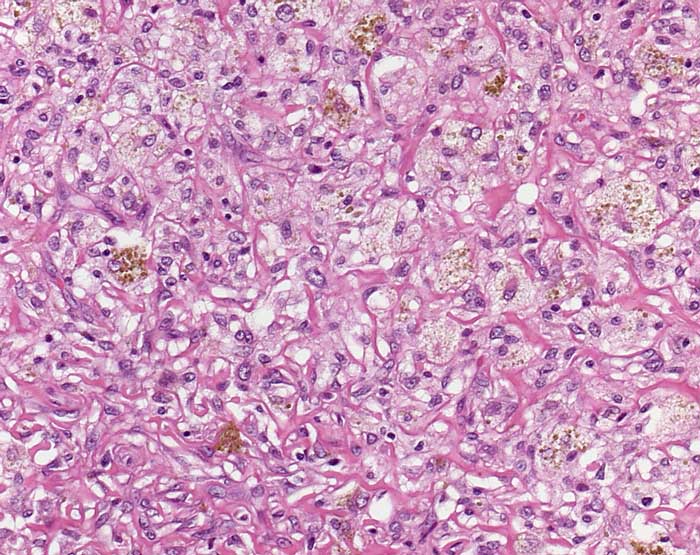

Fett- und eisenspeicherndes Fibrohistiozytom

Zwischen hyalinisiertern Kollagenfasern Gruppen von hellen Zellen mit reichlich schaumigem Zytoplasma. Ein Teil der Schaumzellen enthält zusätzlich braungelbe Sideringranula.

Brauner eingesenkter Knoten am Oberschenkel

Histologie

200